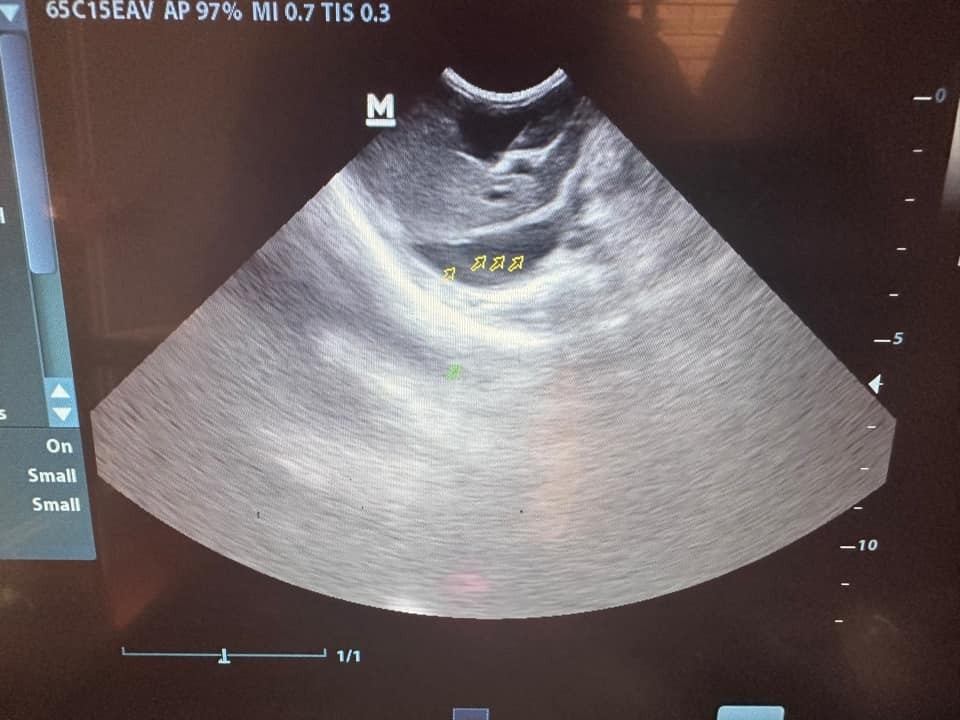

Hình ảnh chụp siêu âm chú mèo do U.N đăng tải trên trang cá nhân